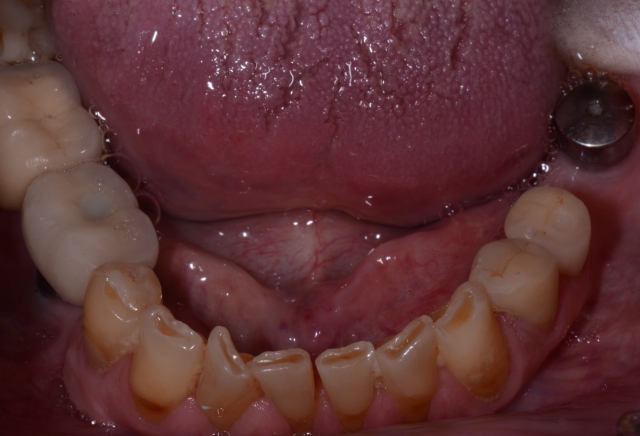

During the oral examination, I recognized that Roger had three of the syndromes we discussed above: extreme worn dentition, xerostomia, and GERD. The damage was extensive and left his dentition in an extremely catastrophic state.

At this point, my job was to educate him as to the true state of his dentition. A patient doesn’t always recognize the gravity of the situation until it’s too late; it becomes our responsibility to inform them and educate them as to the consequences of these conditions.

This is a great time to enlist the skills taught at Spear. The Treatment Planning With Confidence course specifically equips dentists to address these challenges. For example, knowing how to illustrate the patient’s true condition with 35 mm photography is a powerful teaching tool that not only identifies the disease processes but also effectively educates the patient as to their best restorative option.